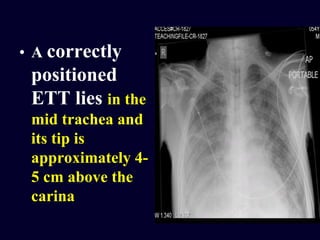

• A correctly

positioned

ETT lies in the

mid trachea and

its tip is

approximately 4-

5 cm above the

carina